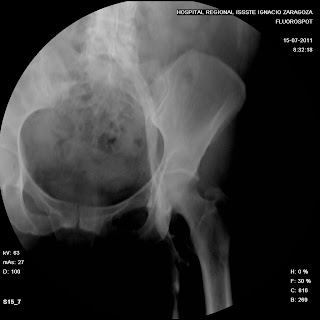

FLEBOGRAFIA (extremidades inferiores)

"FLEBOGRAFIA DE LOS

MIEMBROS INFERIORES"

(TAMBIEN CONOCIDA COMO ASCENDENTE O PELVICO)

La flebografia es un estudio radiologico el cual consiste en la Introducción de un MC hidrosoluble en el “Torrente Venoso” para observar radiologicamente los Transtornos de las Venas y de sus Valvulas.

Mostrando el grado y magnitud del daño, asi como el tiempo de circulacion.del medio de contraste

"PREVIA RADIOGRAFIA DE LA REGION ANATOMICA A EXPLORAR”

žEl MC se inyecta lentamente y bajo control fluoroscopico

žAl observar el llenado de las venas profundas e iniciarse la comunicación a las venas superficiales de las piernas.

žSe despoja de la ligadura el tobillo y se toma la primera placa en proyeccion AP y LATERAL.

ž Para observar las comunicaciones venosas en 2 incidencias diferentes.

žA continuacion se centra la rodilla y se toma Rx de rodilla AP con la ligadura inferior aun colocada y otra sin ella .

žFinalmente se toma una incidencia lateral u oblicua de rodilla

Posteriormente se centra el muslo abarcando la porcion distal y se elimina la ligadura.

Tomando una Rx de muslo y otra en su porcion proximal, tratando de visualizar el nacimiento de la vena iliaca.

žPor ultimo se centra a la altura de la pelvis o cadera, de manera que permita observar la union de las venas femorales con la cava inferior, dando un ligero masaje en pantorrilla y muslo o elevando manualmente las piernas del pte y tomando AP de pelvis al obsevar la llegada del MC ala vena cava.